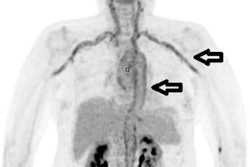

For F-18 fluorocholine PET/CT, the typical appearance is increased tracer uptake relating to a well-circumscribed nodule adjacent to the thyroid, or within the neck or upper mediastinum. Optimizing the PET window settings may help to identify the most accurate focus and thus improve detection of small lesions on the CT component, the Imperial team recommended.

"In [F-18 fluorocholine] PET/CT examinations of the ectopic glands, concordance between second-line imaging is often extremely helpful in cases of unusually located ectopic glands, for preoperative planning, and to minimize risk of morbidity, including scarring and nerve damage," they noted.